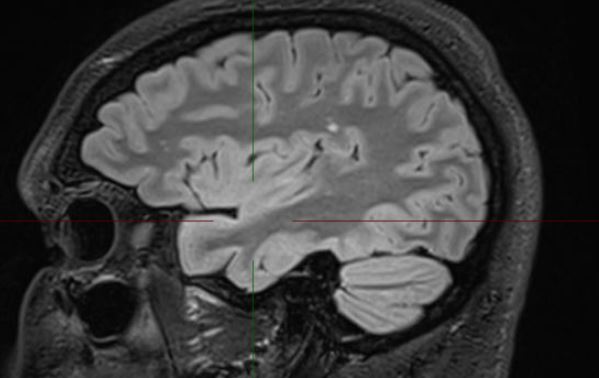

The MRI demonstrates a juxta-cortical, linear lesion in the white matter of the left post central gyrus extending medially to above the insular cortex. There is no mass effect and no enhancement. The nature of the lesion is unclear and does not relate to any of his symptomatology. His loss of consciousness almost certainly was related to a very large binge on alcohol, with very high blood alcohol levels. There is no history of any right facial or any other sensory symptomatology, nor of any episodic or persistent language dysfunction. There is no history of previous cranial trauma. His perinatal and developmental history is unremarkable.

In addition to the above lesion there are a few other punctate white matter lesions. It is presumed that these are old and have been discovered coincidentally as they do not relate to any past or recent symptomatology and are therefore "asymptomatic". I discussed the case with experienced neuroradiologist who reports that the lesions appear "innocuous".  The case also makes the point that diagnostic tests may result in a lot of harm; in this instance the patient was effectively "medically deported" within 24 hours of the scan having been done in a highly developed country. If the EEG is misinterpreted, the patient's problems will only be compounded. His EEG was normal for 72 hours; the rationale for performing it for this duration will be discussed at a later stage